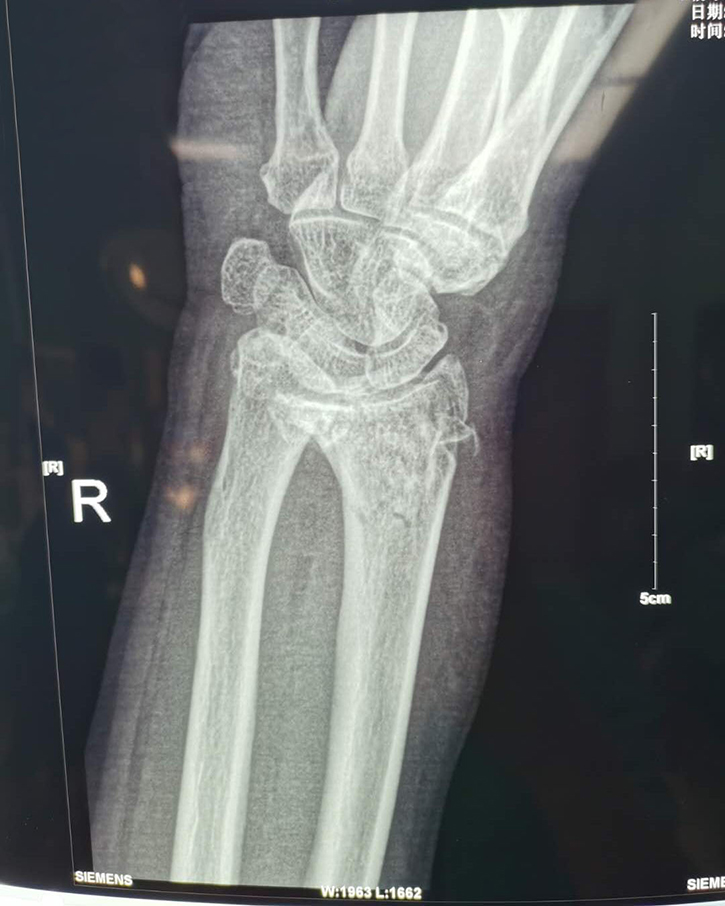

常州鼎健醫(yī)療器械有限公司、弘慈醫(yī)療集團(tuán)均屬于中信產(chǎn)業(yè)基金控股的醫(yī)療企業(yè),而鼎健醫(yī)療作為弘慈醫(yī)療重要戰(zhàn)略合作伙伴的骨科耗材供應(yīng)商,從弘慈醫(yī)療旗下弘慈醫(yī)院的臨床需求出發(fā),提供最適宜的骨科耗材產(chǎn)品和技術(shù)支持,助力弘慈醫(yī)療水平的持續(xù)提升。通過產(chǎn)業(yè)基金領(lǐng)導(dǎo)協(xié)調(diào)支持,供應(yīng)鏈的推動(dòng),達(dá)成強(qiáng)強(qiáng)聯(lián)手合作,6月22日,唐山弘慈醫(yī)院聯(lián)手鼎健團(tuán)隊(duì)首次合作開臺(tái)完成橈骨遠(yuǎn)端骨折鎖定鋼板置入手術(shù)。

這次手術(shù)由唐山弘慈醫(yī)院骨科主任宋曉明與鼎健團(tuán)隊(duì)于手術(shù)前共同討論手術(shù)方案,以鼎健新上市產(chǎn)品橈骨遠(yuǎn)端鎖定板為患者提供手術(shù)治療。宋曉明主任在手術(shù)結(jié)束后表示對(duì)鼎健醫(yī)療的骨科產(chǎn)品和技術(shù)給以高度肯定,患者也對(duì)這次的手術(shù)表示非常滿意。未來,鼎健醫(yī)療將繼續(xù)聯(lián)手弘慈醫(yī)療,積極應(yīng)對(duì)新常態(tài)下醫(yī)療格局新變化,為弘慈醫(yī)療提供領(lǐng)先的骨科產(chǎn)品和臨床解決方案。